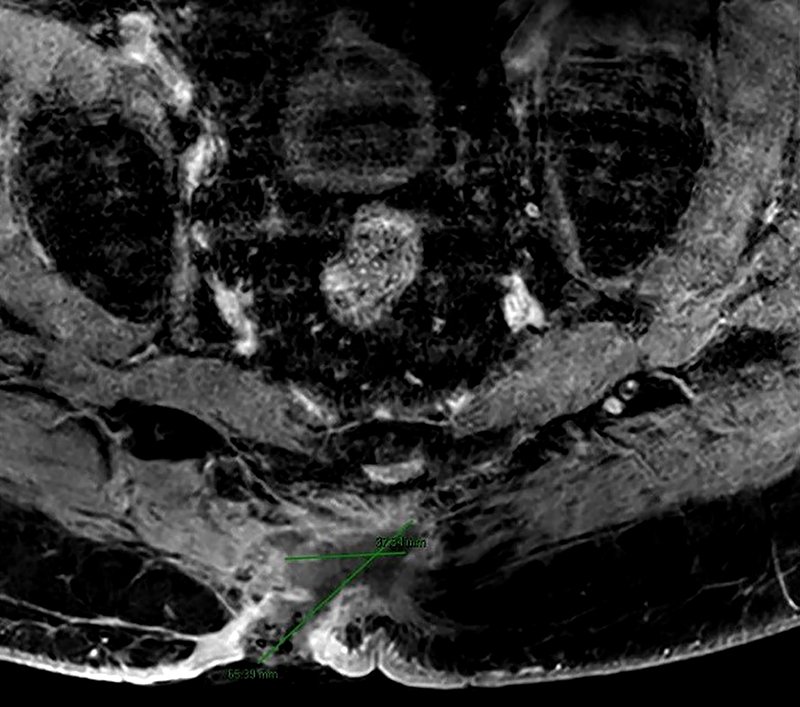

Figura 2: RMN como estadiaje de afectación local. Afectación desde plano muscular y fascia prevertebral hasta tejido cutáneo.